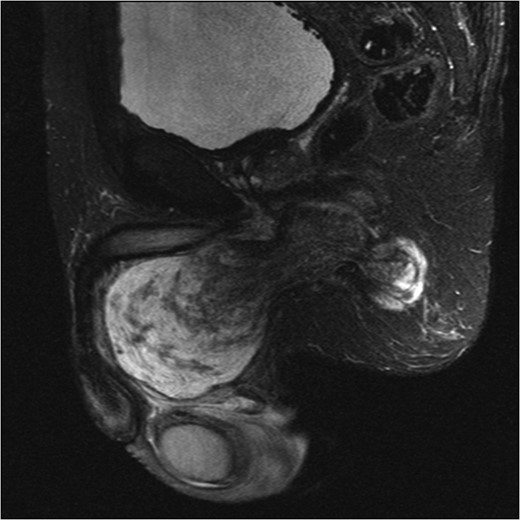

An initial ultrasound confirmed a well-defined heterogenous encapsulated solid mass with internal vascularity. An abdominopelvic MRI revealed a 5.4 cm × 7.2 cm × 15.7 cm solid-cystic well-defined lobulated mass within the perineum separate from the testicles, adjacent to the penis and extending to the right ischial fossa and the obturator internus muscle (Fig. 1). Anteriorly the mass displaced the penile urethra and bulb and the anal sphincters without direct involvement (Fig. 2). There was no locoregional or para-aortic lymphadenopathy.

MRI abdomen and pelvis T2 weighted sequence coronal view demonstrating well-defined heterogeneous mass within the perineum.

MRI abdomen and pelvis T2 weighted sequence sagittal view showing a predominantly cystic mass with scattered solid components within perineum.